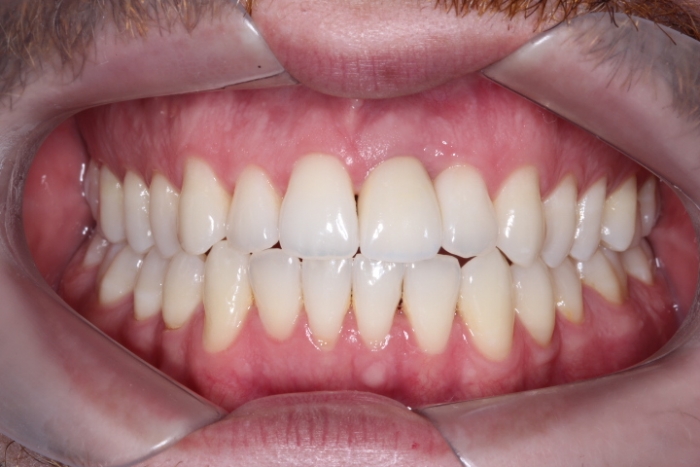

Sorriso Final, Novembro de 2015